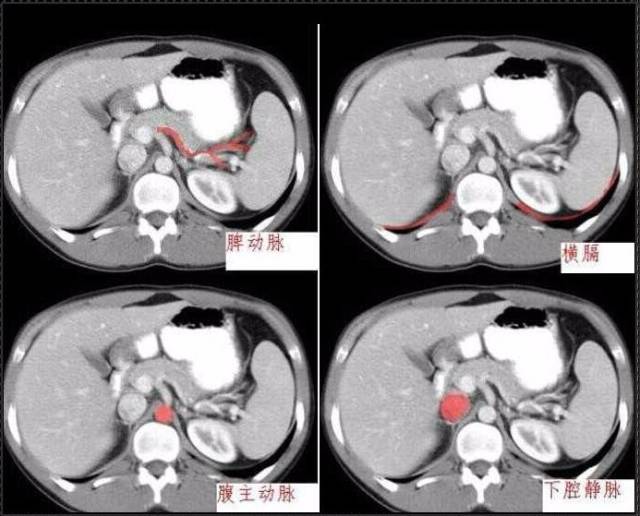

秒懂:腹部 CT 看這篇就夠